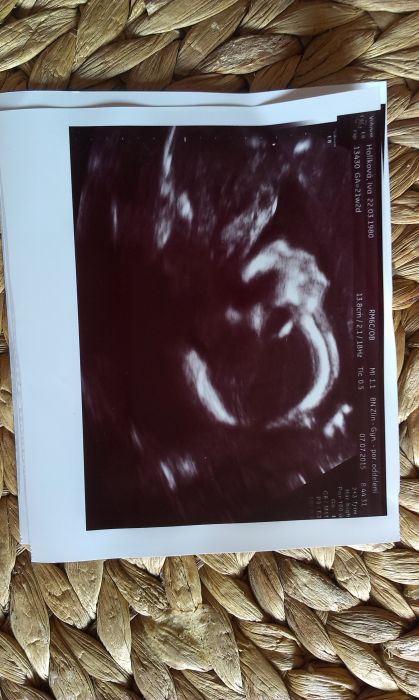

Ahoj holky, tak mam po velkem ultrazvuku:-),cekame holcicku,jak uz nam minule bylo naznaceno.Ted je to na sto procent:-).Važí cca 450gr,meří kolem 26cm..Tak jsem rada,že jsem ji po deseti tydnech videla,že je zdrava a vse,jsem dnes jak na radostnem mracku..Je to asi opravdu zatim nejprijemejsi čast teh.